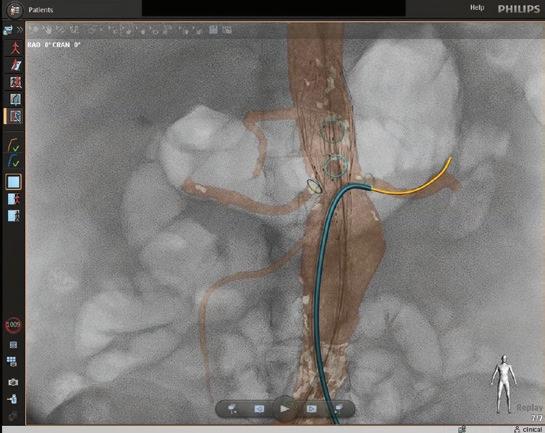

FORS Technology Enhances Visibility and Reduces Radiation Exposure during EVAR

Light refracted through optical fibers generates real-time images of endovascular devices.

Endovascular repairs are done in a hybrid cardiovascular operating room with advanced imaging equipment, a fluoroscopy unit and traditional operating suite. At UMass Memorial Medical Center, the hybrid OR is also equipped with Fiber Optic RealShape (FORS) technology. Surgeons there were the first in the nation to use FORS for a complex endovascular aortic aneurysm repair (EVAR). The technology gives operators better imaging and more flexibility in maneuvering endovascular guidewires and catheters for EVAR, while also reducing dependence on fluoroscopy.

A new technology developed by Philips dramatically improves visibility while also reducing dependence on fluoroscopy. In 2021, UMass Memorial Medical Center vascular surgeons became the first in the nation to use FORS, a technology that generates real-time images of endovascular devices by refracting light through optical fibers. Only two other hospitals in the U.S. and three outside the country are currently using it.

Instead of the ionizing radiation of fluoroscopy, FORS technology uses light refracted through optical fibers to provide 3D tracking of endovascular guidewires, catheters and devices. FORS technology has the potential to reduce a patient’s radiation exposure by as much as 75% during endovascular complex aortic aneurysm repair.

Fiber Optic RealShape technology enhances visibility as the operator moves devices through the arteries. The 3D images enable the team at the Center for Complex Aortic Disease to view progress and movement from any angle.

Imaging advantages

In addition to reducing the need for fluoroscopy, FORS technology enhances the visibility as the operator moves devices through the arteries. The real-time images produced are three dimensional, so the EVAR team can view progress and movement from any angle. The technology also allows for zooming in and having multiple projections on-screen at once.

“This enables me to always keep the full extent of the guidewire in my field of vision,” Schanzer said. “Then I can advance the FORS catheter over the wire to get it in position. The FORS system shows which portion of the guidewire or catheter is in front of the other, making all endovascular interventions easier and safer.”

The FORS images are displayed on top of, and in alignment with, anatomical patient images created through digital subtraction angiography (DSA) or computed tomography (CT), both of which are black and white. With DSA or CT images alone, it can be difficult to determine the exact placement of the catheter, but with FORS technology, it can be seen in color in the foreground.

“The system is very intuitive and truly represents a new era in device guidance,” Schanzer said, adding that having a color image has an additional benefit. “Until I started using FORS, I hadn’t realized how much operator fatigue there is when you’re only looking at different shades of gray to visualize everything. It’s become very apparent to me that the bright yellow and blue on top of the gray background really decreases that strain, especially when you’re looking at previous stent grafts and wires.” ◼